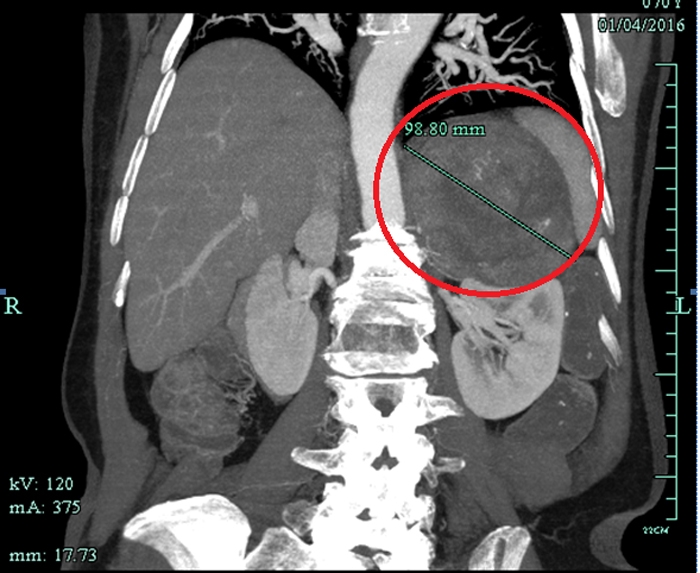

CT檢查意外發(fā)現(xiàn)巨大腫瘤

??? 原來,朱老太與高血壓相伴已經(jīng)有20多年了,一直服用降壓藥,而且血壓忽高忽低不穩(wěn)定。一個(gè)多月前,因?yàn)橹匕Y肺炎在當(dāng)?shù)蒯t(yī)院住院,行胸部CT檢查的時(shí)候發(fā)現(xiàn)左上腹有一個(gè)十多公分的巨大腫瘤。家人馬上把朱老太送到省城一家大醫(yī)院住院,磁共振檢查后考慮左腎上腺惡性腫瘤,需要做大手術(shù)。家人擔(dān)心老人瘦弱的身體承受不了開腹手術(shù),多方打聽后得知市人民醫(yī)院泌尿外科做腹腔鏡手術(shù)技術(shù)成熟,就找到了萬里軍醫(yī)師。萬醫(yī)生初步診斷為左腎上腺嗜鉻細(xì)胞瘤,考慮是惡性腫瘤,雖然腫瘤體積巨大,但能在腹腔鏡下切除腫瘤。

患者CT影像

??? 萬里軍仔細(xì)看了CT和磁共振片后,認(rèn)為腫瘤與腎靜脈、腹主動脈關(guān)系密切,建議用衢州市人民醫(yī)院最新引進(jìn)的320排螺旋CT做個(gè)血管成像,明確腫瘤與這些重要血管的關(guān)系。同時(shí)啟動了多學(xué)科會診治療(MDT)程序,邀請呼吸內(nèi)科、心血管內(nèi)科、內(nèi)分泌科、麻醉科、重癥醫(yī)學(xué)科、輸血科等相關(guān)科室進(jìn)行會診,充分估計(jì)術(shù)前、術(shù)中和術(shù)后可能遇到的問題,制定了幾套方案。與患者及家屬進(jìn)行溝通,獲得他們的配合信任。